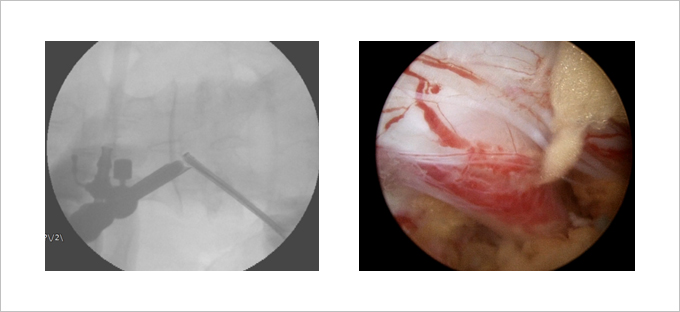

젓가락처럼 가느다란 내시경 관(지름 약 6mm 굵기)을 피부에 찌르듯이 삽입해 병소가 있는 뒤쪽 섬유륜 만을 선택적으로 치료합니다.

디스크 조영술로 본 시술 장면 가느다란 내시경 관이 들어가서 레이저로 뒤쪽 섬유륜을 치료하고 있다.

내시경 관은 지름이 6mm에 불과하여 시술 후 흉터가 남지 않는다.